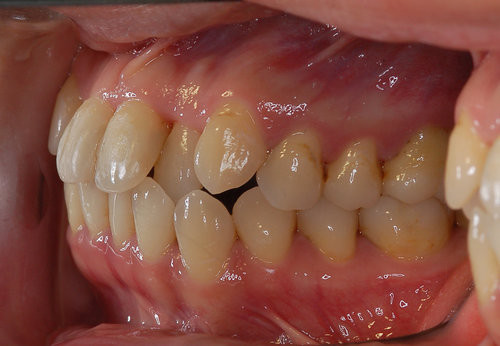

双颌前突

双颌前突矫正过程中可能会出现的小问题是牙齿脱矿和食物嵌塞。牙齿脱矿是指在矫正过程中,托槽周边或牙龈边缘位置出现的白垩色变化,一般是由于患者在矫正过程中没有仔细刷牙,没有维护好口腔卫生环境,致使牙齿表面的细菌产酸而使牙齿的颜色和实质发生变化。